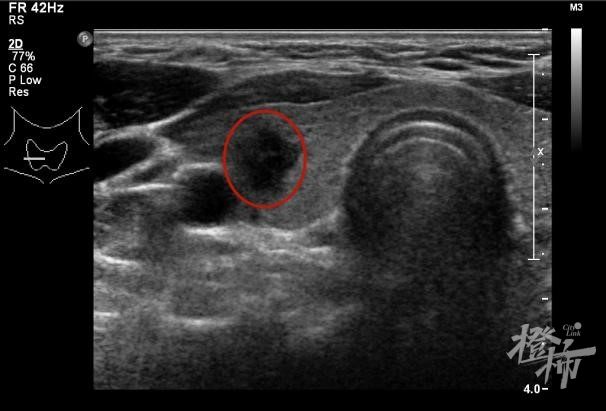

超声检查提示一个5.48mm×7.39mm左右大小的结节 医院供图